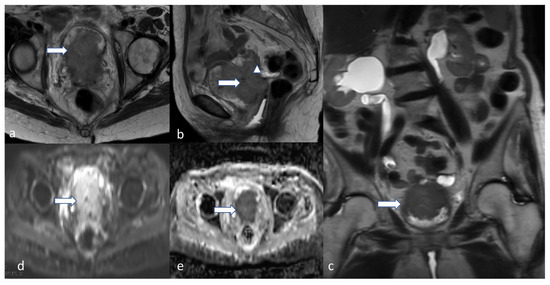

5.3. Magnetic Resonance Imaging (MRI)

4.3. Stage III

5. Role of Imaging Modalities